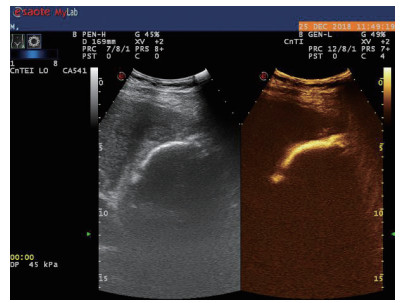

1.3 手术过程 1.3.1术前经肘静脉超声造影:行PTGBD前半h经肘静脉快速团注SonoVuel 5 mL,在对比脉冲序列造影成像模式下进行观察,根据不同组织造影剂凝聚的时间及浓度差异,判断胆囊周围组织黏连程度、胆囊壁完整程度(图 1),如出现胆囊壁造影剂充盈缺损(图 2、3),则考虑胆囊壁坏死或穿孔,根据静脉造影情况选择合适的置管入路,避开胆囊穿孔的部位及黏连组织。

| 图 2 穿刺后经引流管超声造影,显示置管路径(箭头处) |

术后再次经肘静脉超声造影同时经引流管超声造影:PTGBD后,再次经肘静脉快速团注SonoVuel 2 mL,在造影成像模式下进行观察肝脏被膜、胆囊床穿刺路径有无造影剂外渗,腹腔内有无外渗凝聚的造影剂,判断有无活动性出血及出血程度,如判断出血速度快、出血量较大,考虑动脉性出血,及时改为开腹或腔镜手术止血。PTGBD术后经引流管超声造影,置管成功后快速抽出胆囊内残留胆汁,减轻胆囊压力后,在超声造影模式下直接经引流管注入配制待用的稀释声诺维造影剂20 mL,实时动态的观察造影剂在胆囊腔内的充盈范围(图 2、3),评估引流管的通畅程度及引流范围、观察其在胆囊腔内的位置走形及卷曲情况、观察胆囊周边及腹腔内有无造影剂外渗。如患者腹痛症状加剧,结合经引流管超声造影判断有胆汁漏出表现,应持续监测观察患者生命体征及保守治疗效果,必要时及时改行开腹或腔镜手术治疗。

超声造影是利用超声造影剂微泡(本组应用的是声诺维超声造影剂微泡)在低机械指数声波照射下发生共振,产生线性及非线性谐波回声信号,形成造影增强图像的技术,是近年来新兴的超声技术,具有实时、可连续观察、无辐射、可重复性好、毒不良反应少等优势,为临床提供了全新的诊疗手段[14]。经肘静脉注入的标准配置超声造影剂是一种血池造影剂,可以反映组织的血流灌注情况同时亦被广泛应用于肝、脾、肾等实质性脏器破裂的诊断,其诊断的敏感性及特异性均明显优于二维超声,且与增强CT有较好的一致性[15-16]。本组病例术前经肘静脉注入标准配置造影剂后,胆囊壁均显影增强,胆囊穿孔及周边积液处表现为造影无充盈区,穿刺置管后再次静脉路超声造影,迅速发现术后出血部位且可敏感评估是否为活动性出血(经手术证实)。除1例因活动性出血中转腹腔镜手术外,其余32例置管成功后经引流管口注入稀释造影剂20 mL(1:200稀释),评价引流管位置、引流范围及是否出现胆汁外漏取得良好效果,所有引流导管均能够清晰显示引流导管置入路径、引流管形态及引流范围,引流管置入恰当者,头端位于胆囊内,全管显影清晰,造影剂弥散区域与胆囊大小吻合; 置管后胆汁漏出者,可见造影剂沿引流管周边渗出[17-18],本组中3例出现造影剂外渗,其中两例渗出范围局限于胆囊床附近,未渗出至游离腹腔,患者腹痛症状稍有加剧,经胆囊减压及对症处理后好转,其中1例见造影剂渗出至肝肾间隙,患者腹痛症状加剧明显,考虑置管位置不当,余行急诊腹腔镜手术治疗,术中证实为系膜胆囊,且可见引流管侧孔部分外露。笔者的经验是,术前选择静脉路超声造影有助于对胆囊情况的评估及穿刺点的选择,术中正确选择穿刺针的入路有利于提高穿刺引流的成功率。首先是胆囊穿刺部位的选择应选择在靠近胆囊颈侧,此处胆囊位置比较固定,受体位影响较小,且胆囊床结缔组织较为固定,有助于将漏出胆汁包裹局限,其次是进针方向与胆囊床尽可能保持垂直,减少进针位置的偏移,同时置管成功后应即刻尽量抽尽胆囊内的感染性胆汁,生理盐水冲洗后行经引流管稀释超声造影有助于判断置管位置、引流范围及是否出现胆汁漏出,减少不必要的并发症发生率。穿刺引流后可以根据患者的营养状况待窦道形成稳定后择期拔除引流导管。对全身情况改善适合手术治疗且有手术意愿者可以考虑择期胆囊切除术。